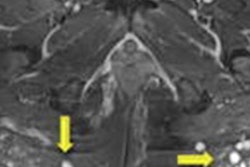

In this edition's Insider Exclusive, we're highlighting a study conducted by researchers from Emory University in Atlanta who found using MRI to guide a procedure called stereotactic laser corpus callosotomy (SLCC) produces comparable outcomes to open surgery -- and also improves robotically guided SLCC.